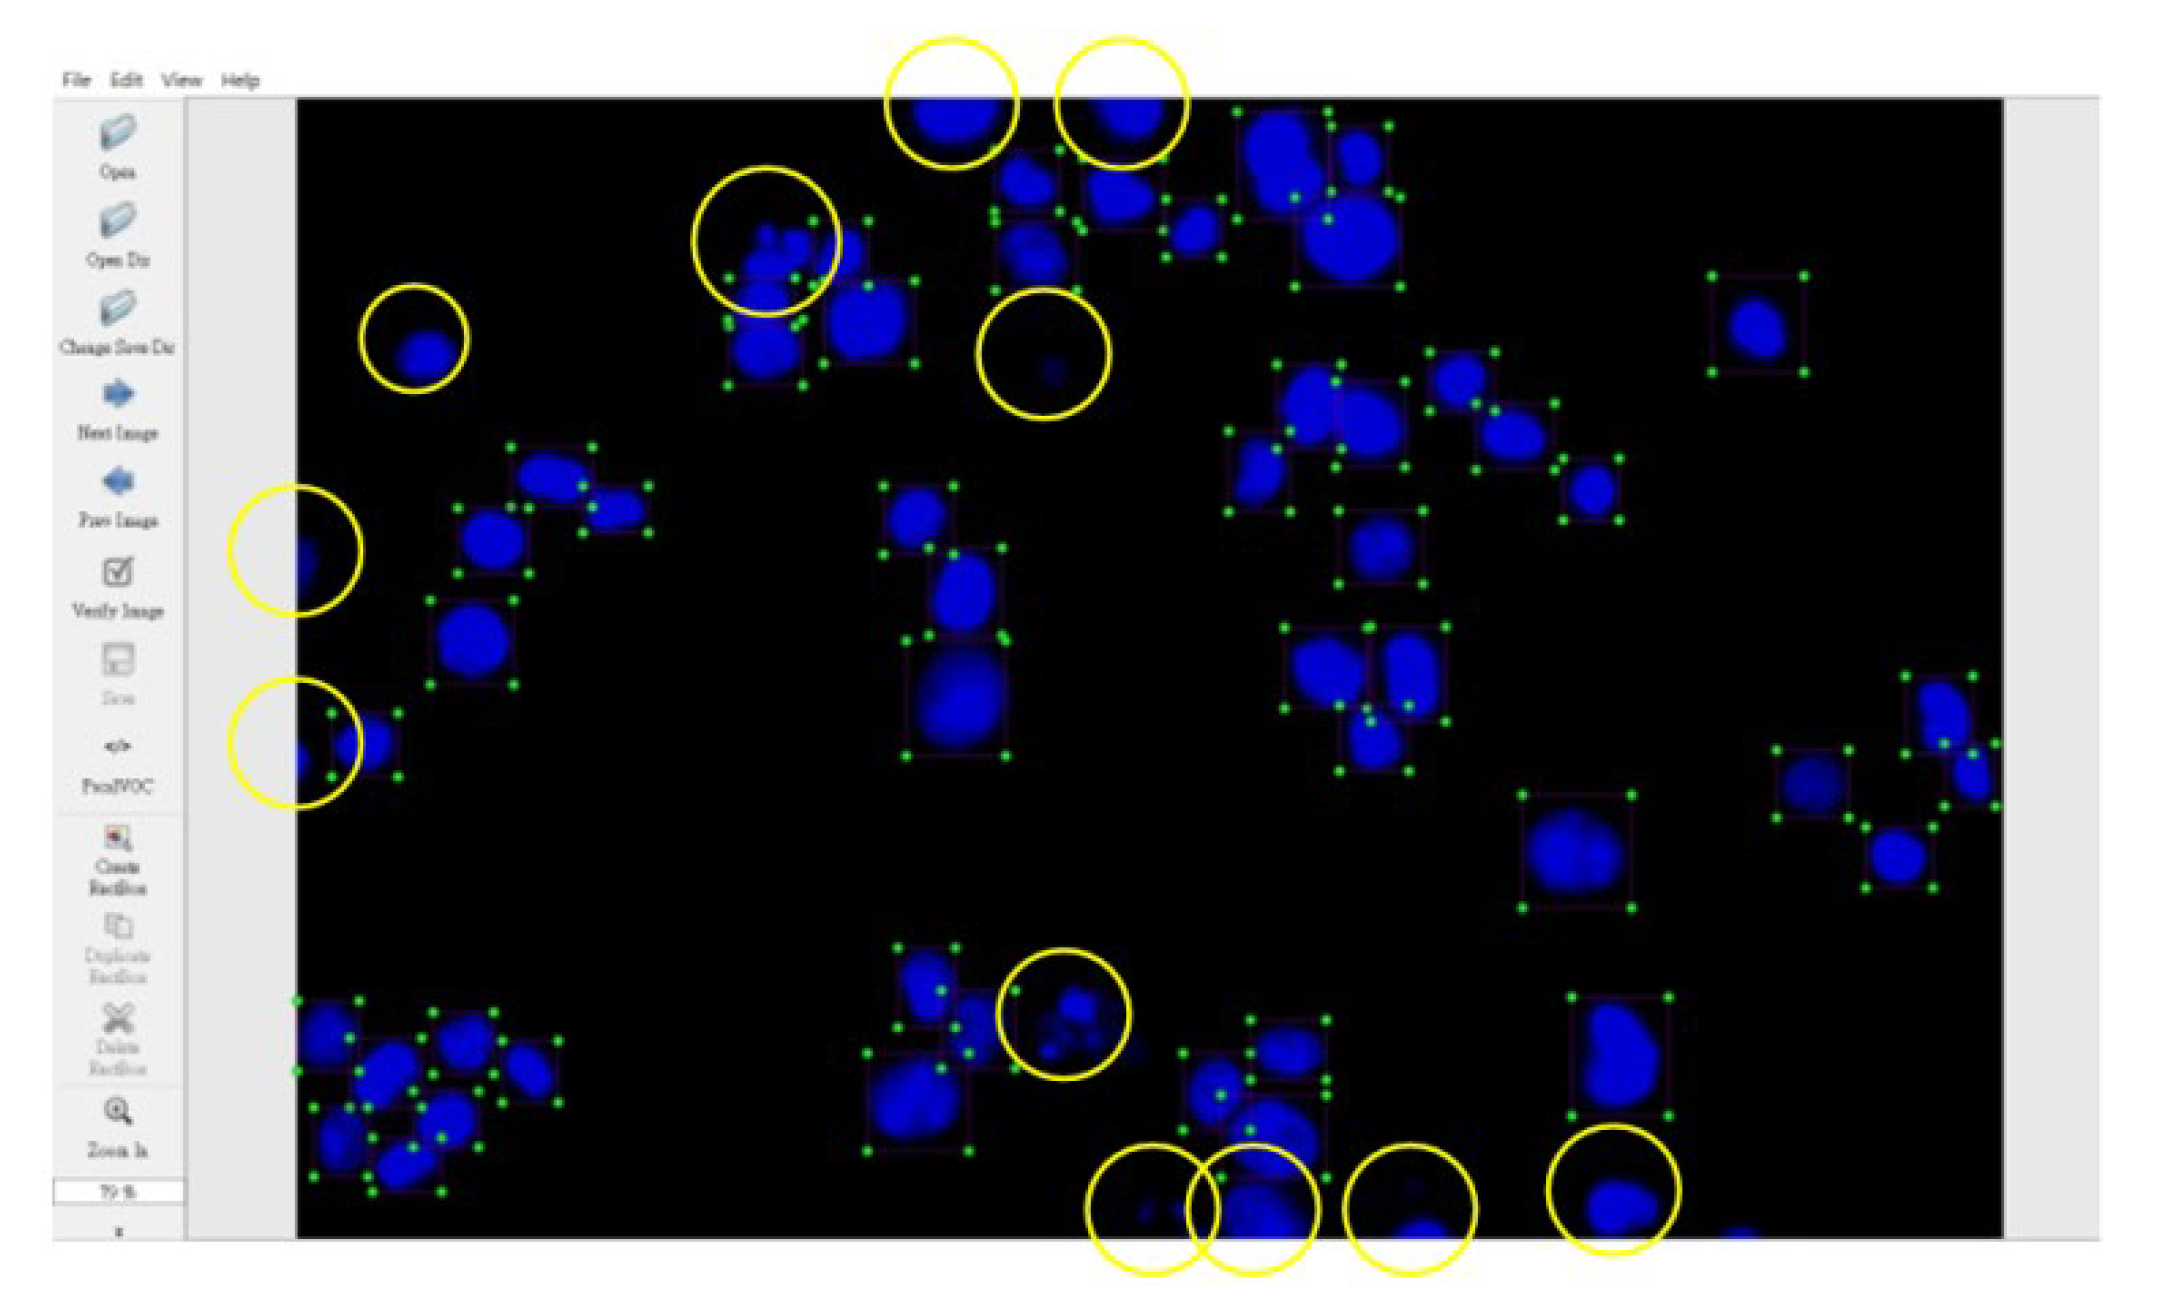

Consequently, the cell nuclei were the primary analysis targets. The samples of normal cell nuclei were trained only via the proposed method. We collected 92 images for training the neural network (23 images for the model parameter verification and 300 images as the testing data for the four colon cancer cell lines) and labeled the normal cell images using a tool called LabelImg [40]. There were approximately 50 cell nuclei samples in each image. The ratio of the number of training and verification images was 80%: 20%. The region selection of the normal cell nucleus for rectangular box annotation was performed according to the literature [12] and our practical experience with inspection (see Figure 10). In Figure 10, each nucleus in a rectangular box (a purple box with four green points) represents a cell nucleus sample. The abnormal cell nuclei are not annotated in Figure 10 (the yellow circles represent the abnormal cell nuclei). The YOLO algorithm was used to perform 100,000 iterations of training for the normal cell nucleus images. A chart of the loss function in training by the YOLO algorithm is shown in Figure 11 (the average loss was 0.3928). We separated the images of the cytoskeleton and the cell nuclei by extracting the red and blue elements. The same method was also used to recognize the cell nuclei specifically. For this application, the nucleus was the only recognized object. The rectangular box was then used to mark the cell nucleus. Figure 12 (for HCT116 cell) shows the results. The parameters of the YOLO algorithm were the following: The number of training samples was set to 24, and the number of segments to be trained was set to 8. The gradient descent with momentum was set as 0.9, and the weight–decay ratio was set as 0.0005. The learning rate was set as 0.001, and the activation function was Leaky ReLU. The learning policy was “Step”.

Figure 10.

Region selection of the normal cell nuclei for rectangular box annotation using LabelImg (the yellow circles represent abnormal cell nuclei that were not annotated).